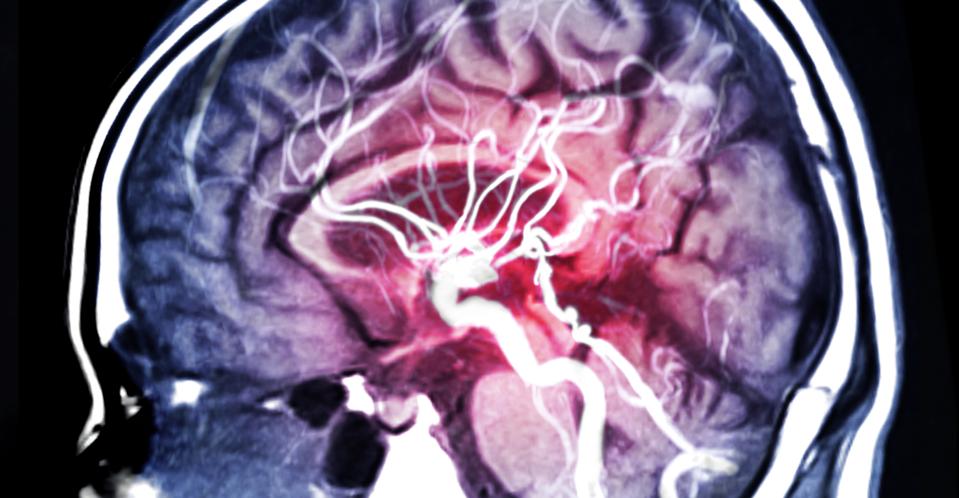

We now know that traumatic brain injuries (TBI), particularly concussions, are very common among football players. Symptoms of mild TBI include headache, confusion, nausea, dizziness, memory and mood changes, and a brief loss of consciousness. Moderate-to-severe TBI symptoms can include persistent headaches, repeated vomiting, convulsions, agitation, slurred speech and brain infections such as meningitis. Additional complications of TBIs include addiction, mental illness, coma and brain death.

Magnetic resonance angiography (MRA) of blood vessels in the brain. MRA imaging can reveal stenosis … [+]

Getty“We’re at an exciting time,” according to TBI expert, Ross Zafonte, D.O. But he said we need to frame the discussion of athlete brain health based on childhood experiences. “Who did you used to be? What were you like as a child? What exposures did you have?” were sample questions posed by Dr. Zafonte, Chief of Physical Medicine and Rehabilitation, Massachusetts General Hospital.